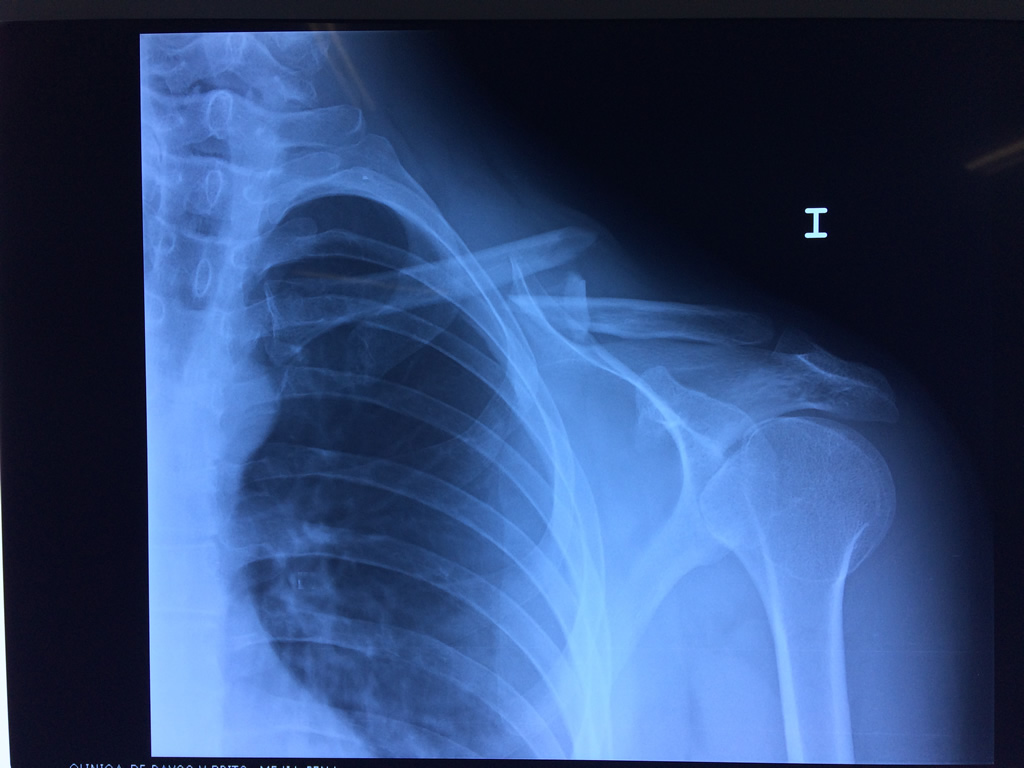

La clavícula es un hueso largo, con forma de "S" itálica, situado en la parte anterosuperior del tórax. Junto con la escápula forman la cintura escapular. Se puede palpar por toda su longitud y se extiende del esternón al acromion de la escápula, siguiendo una dirección oblicua lateral y posterior.